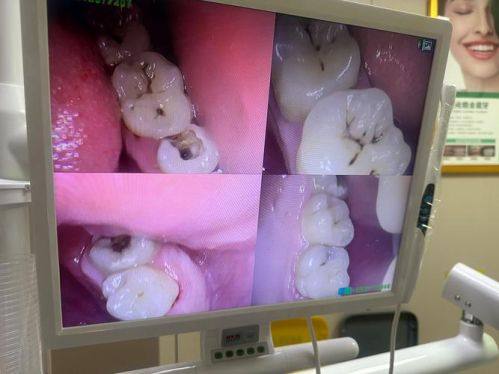

根管治疗:借助精良的数字化设备精细定位病灶,由专精医生操作,能有效清除根管内感染物质,缓解牙齿疼痛,保留患牙,治疗过程注重患者舒适体验。